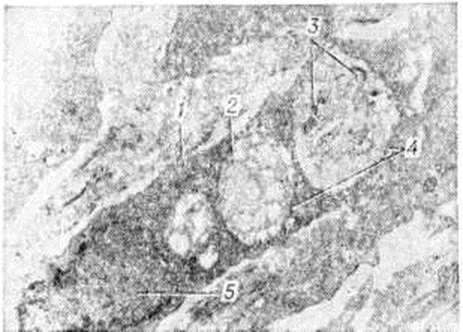

Электронно-микроскопическими исследованиями установлено, что ультраструктура возбудителя Лепра принципиально не отличается от строения других видов грамположительных бактерий. На поверхности микобактерий Лепра выявляется равномерный электроннопроницаемый (осмиофобный) слой толщиной 5—10 нанометров (наружный диффузный слой клеточной стенки). За ним следует осмиофильный слой клеточной стенки толщиной от 3 до 10 нанометров, состоящий из двух очень тонких некоторое, плотно прилегающих друг к другу. Непосредственно к внутренней поверхности клеточной стенки примыкает наружный слой цитоплазматической мембраны (рисунок 1), представляющей собой, как и у других бактерий, трёхслойную мембрану толщиной 7,5—9 нанометров. В бактериальной клетке встречаются 1—2 мезосомы с выраженным полиморфизмом (петлеобразные, везикулярные, трубчатые, пластинчатые, гроздевидные). В цитоплазме выявляется сравнительно небольшое количество рибосом, сферические электронно-плотные включения волютина диаметром 20—50 нанометров, включения, имеющие вид ограниченных мембраной вакуолей (предположительно липоиды), и гомогенные тельца, природа которых остаётся неизвестной. Ядро не имеет определённой формы, расположено в центре клетки вдоль её длинной оси, не ограничено мембраной. Иногда в лизирующихся под воздействием химиотерапии клетках микобактерий Лепра выявляются спороподобные образования (рисунок 2 и 3).

Рис. 1. | ||